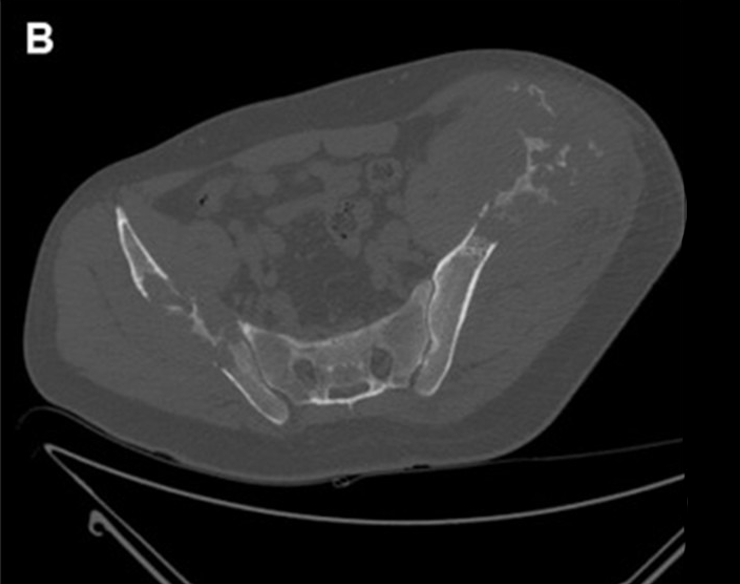

Figure 1: A 56-year-old male patient with two large metastases from renal cancer localized in both iliac bones. (A) panoramic DSA angiogram showing two large hypervascular masses supplied by hypertrophic vessels arising mainly from in internal iliac artery (asterisk). (B) Pre-embolization CT-scan demonstrating the two large lytic lesions of both iliac bones and (C) 6-month follow-up CT showing marked calcification of the lesions.